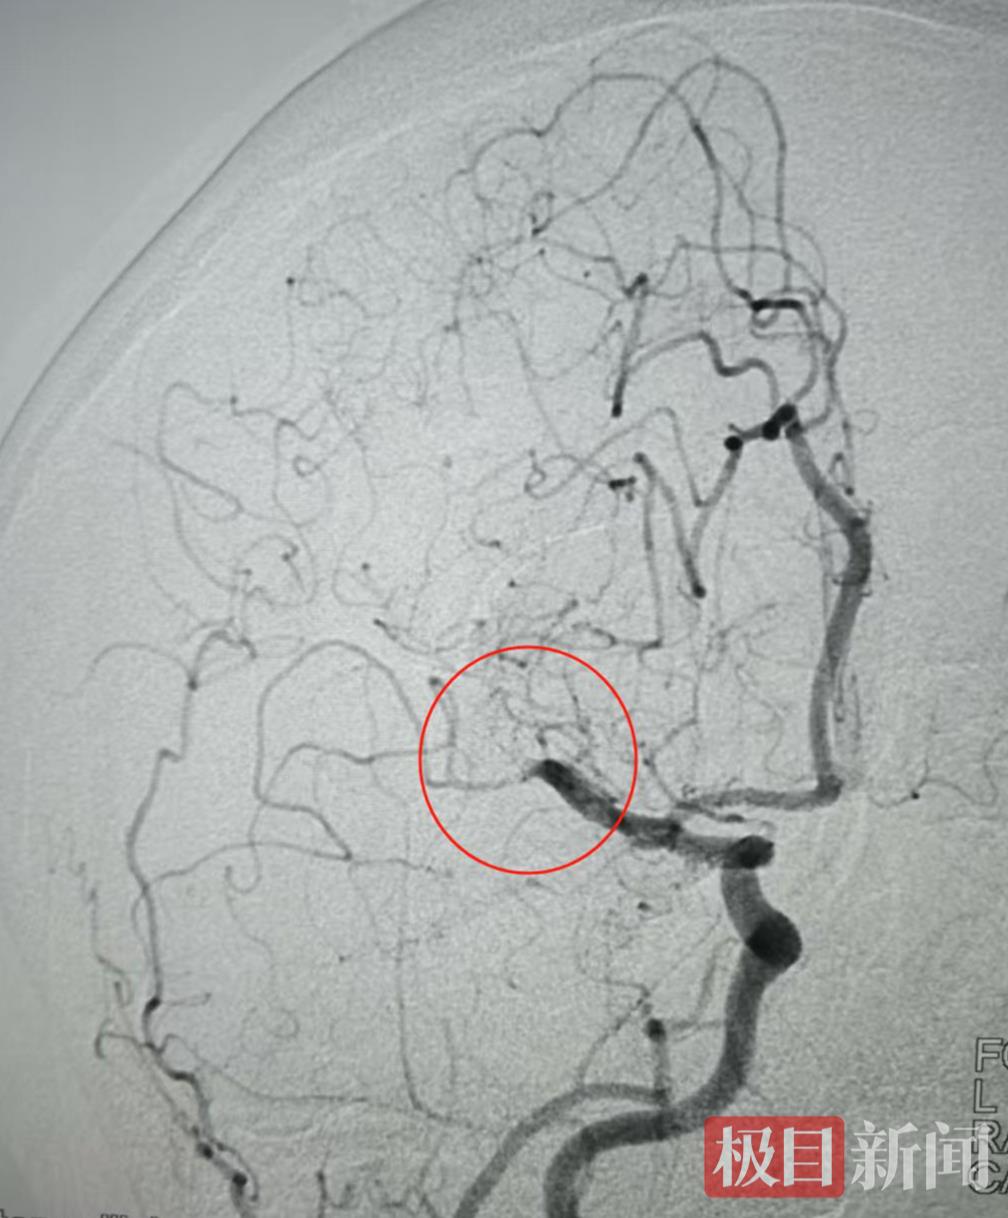

脑血管栓塞处

脑血管栓塞处